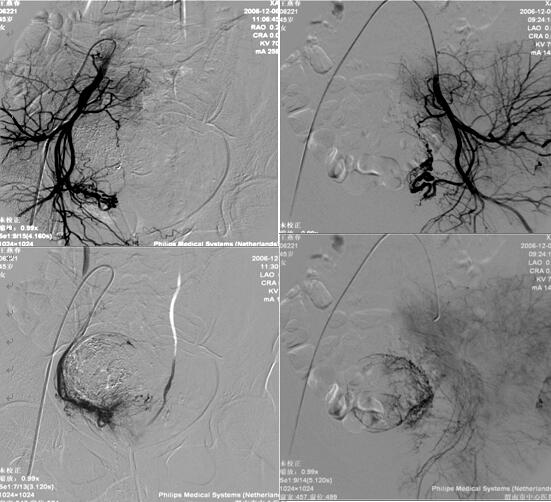

乐鱼手机站入口介入科在李建国主任带领下自2006年开展子宫肌瘤栓塞术,现已完成数百例相关疾病介入治疗,为渭南地区及各县患者提供了全新的子宫肌瘤治疗方法,避免患者子宫全切。子宫肌瘤栓塞术是一种安全有效的治疗方法,是由介入医生经病人腹股沟股动脉导入一导管至肌瘤的血供(子宫动脉)处,释放一些细微颗粒,弹簧圈、或者球囊等阻断肌瘤的血供、供养及出血部位,使肌瘤纤维化,出血停止,肌瘤萎缩。所有经过介入治疗的患者术后大约3-6个月相关症状完全消失。

经子宫动脉栓塞术还可应用于子宫腺肌症、胎盘植入、瘢痕妊娠、前置胎盘及产后大出血等疾病,以下为一例产后大出血患者介入治疗图片: